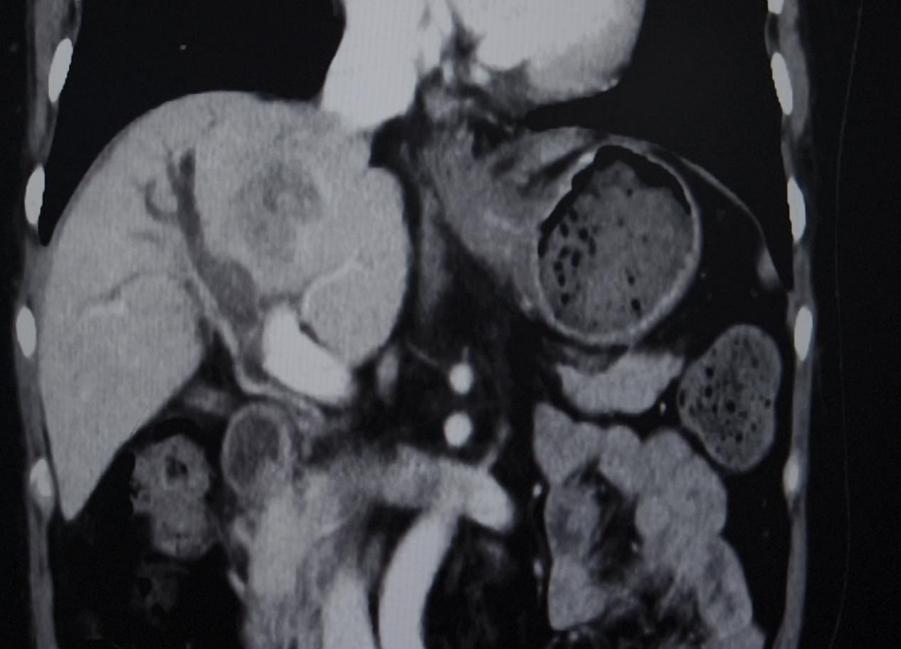

CT(2025.2.18):1、肝右叶异常强化团块影伴周围胆管扩张,考虑肝内胆管癌可能性大,门静脉右支充盈缺损影,考虑癌栓形成。2、脾脏缺如;胆囊、胰腺、双肾及双侧肾上腺未见明显异常

TACE术后28天影像学检查

与2025-02-18日腹部增强片对比示:1.肝右叶多发低密度结节,考虑胆管癌,最大病变内多发颗粒状致密影,考虑介入术后改变,较前病变内坏死增多。肝中静脉局部走行于病灶边缘,管腔未见明显受侵。2.门脉右支起始处少许癌栓,远端未见显影,考虑治疗后改变。3.脾脏缺如;胆囊继发性改变,胆囊窝积液。肠系膜间可见多发稍大淋巴结。

经过三位重建,评估肿瘤体积缩小,肝左叶体积增大,全身PET-CT评估门脉癌栓没有活性,与家属充分沟通病情后决定行手术切除。